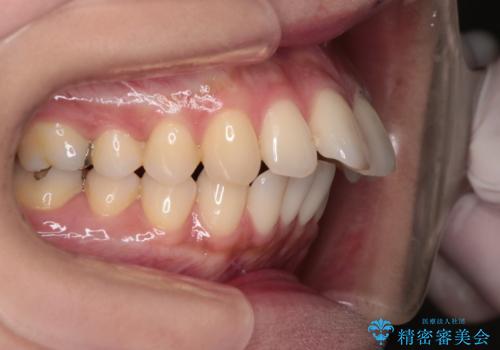

- 上の前歯の突出感を気にして来院された患者様です。

目立たない装置を希望とのことで、上顎左右第一小臼歯を抜歯し、インビザラインにて矯正治療を行うこととしました。

インビザラインにて抜歯矯正を行うと、高頻度で奥歯が咬み合わなくなります。

また、抜歯スペースに向けて奥歯が移動する際、必ず傾斜して移動するため、仕上がりの咬み合わせはワイヤー矯正と比べて明らかに劣ります。

抜歯スペースが閉じてからも咬みにくさ改善のためマウスピース矯正を継続するため、治療期間は長期化します。